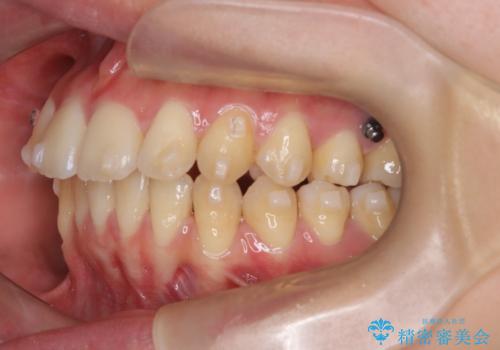

【インビザライン】アンカースクリューを用いた遠心移動

- 前歯の突出を主訴に来院されました。

アンカースクリューとインビザラインを用いて遠心移動を行うことでできる限り前歯を下げて叢生の改善を行いました。

遠心移動を行う際は、患者様にゴムの使用をお願いしております。